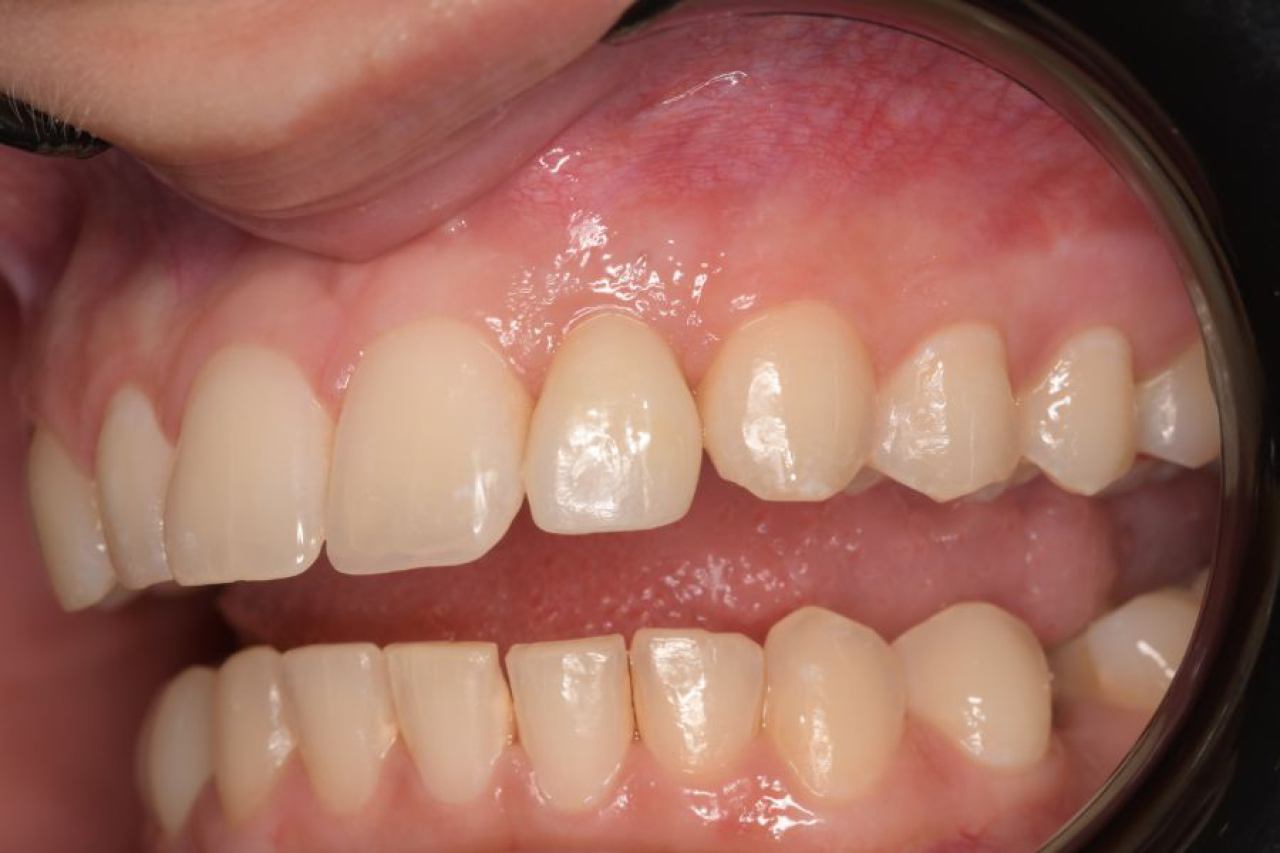

Protetika - mostovi i krunice

Dentalna protetika uključuje fiksne i mobilne radove kojima se nadoknađuje djelomična ili potpuna bezubost. Njihov cilj je povratiti funkciju žvačnog sustava i u konačnici, vrhunsku estetiku.

Marković Dental Clinic u svojoj ponudi ima metalkeramičke radove, potpunokeramičke radove, te u narodu zvane „bezmetalne", odnosno zirkonske radove.